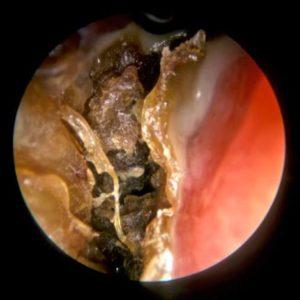

| Атрофический ринит (озена) | Хроническое воспаление слизистой оболочки носа с ее истончением и образованием корок. | Сухость в носу, образование корок, неприятный запах из носа, снижение обоняния. |